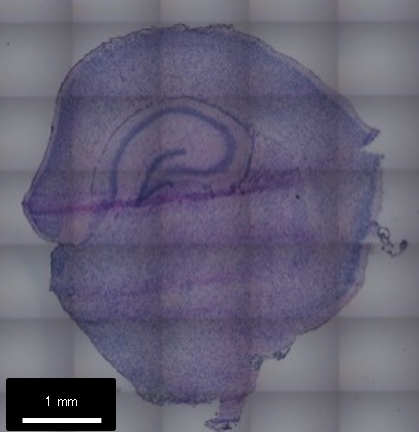

マウス14日齢の脳FFPE切片を対象に実施した空間解析の事例をご紹介します。

- マウスP14 全脳 冠状面

- 切片厚 5 μm

- 組織サイズ約6.8 x 8.8 mm

- シークエンス 30億 PEリード

DNBSEQ-G400, 2 flow cells

- 検出遺伝子数 (各解像度での中央値)

4,081 (Bin200 - 100 x 100 μm単位)

97 (Bin20 - 10 x 10 μm単位)